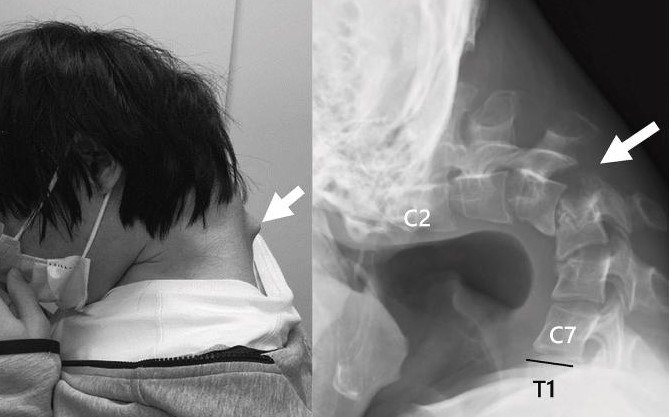

Αποτέλεσμα αυτής της στάσης ήταν να αναπτυχθεί ένα εξόγκωμα στον αυχένα, ενώ ο ίδιος έχασε πλήρως την ικανότητα να σηκώνει το κεφάλι του. Η κάμψη ήταν τόσο προχωρημένη, που το πηγούνι του ακουμπούσε μόνιμα στο στήθος.

Το 2023, ο νεαρός άρχισε να υποφέρει από αφόρητο πόνο στον αυχένα και δυσκολία στην κατάποση, η οποία προκάλεσε ταχεία απώλεια βάρους. Οι ιατρικές εξετάσεις αποκάλυψαν έντονη παραμόρφωση των αυχενικών σπονδύλων, καθώς και βλάβη στην ανώτερη σπονδυλική στήλη – συνέπειες της μακροχρόνιας καταπόνησης και υπερέκτασης των μυών του αυχένα.